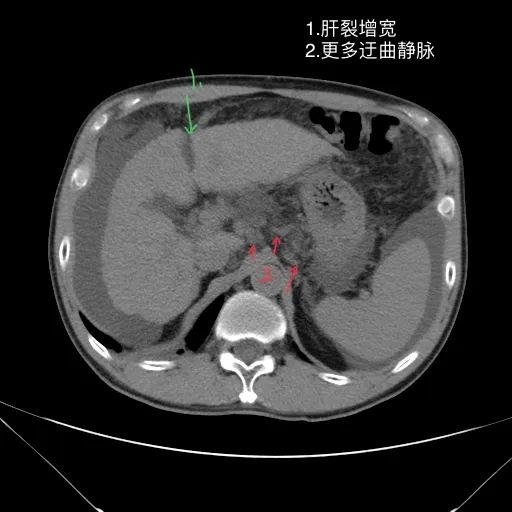

肝脏缩小,包膜凹凸不平,肝裂增宽,各叶比例失衡,肝实质密度不均,肝S4小片低密度影,约cm;胆囊不大,其内未见异常密度影,胆道系统未见扩张;胰腺、脾脏形态、密度、大小未见异常;双肾上腺及双肾形态、密度、大小未见异常,双输尿管未见扩张,膀胱充盈良好,壁光滑,其内未见异常密度影;前列腺未见异常;胃肠道未见充盈,壁未见明确增厚,食管胃底多发迂曲、增粗血管,腹部及腹膜后未见肿大淋巴结;腹水。

1.肝硬化失代偿表现(腹水,食管胃底静脉曲张)。